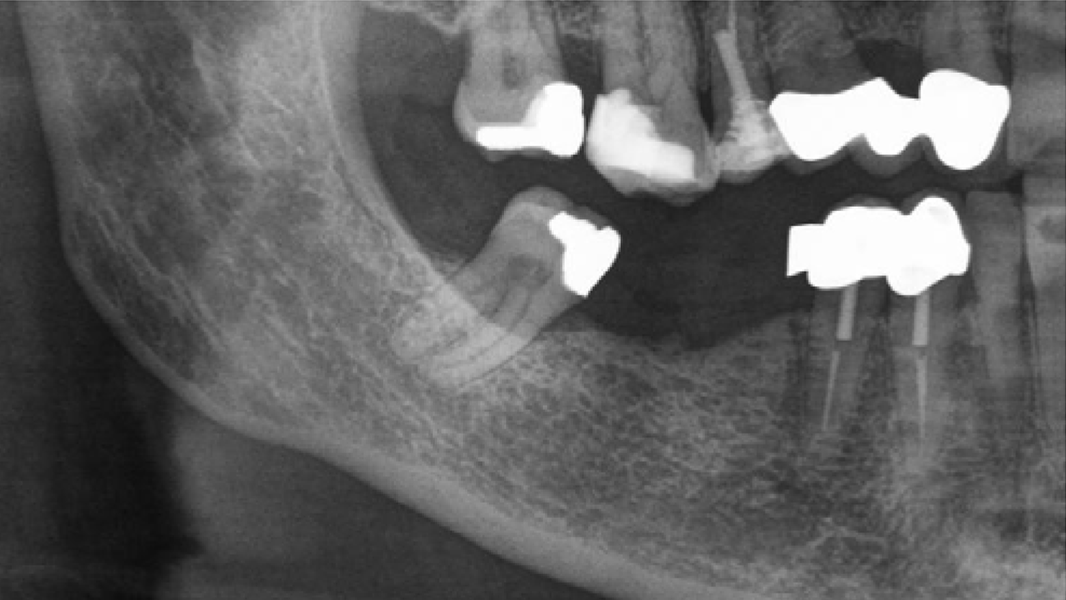

Die rein spongiösen Granulate ermöglichen durch eine zügige Remodellierung einen schnellen Knochenaufbau bei eingegrenzten Defekten, wohingegen das kortiko-spongiöse Material beim Aufbau ausgeprägter knöcherner Defekte für eine längere Volumenstabilität sorgt.

- Die schnelle Remodellierung von MinerOss A verkürzt die Wiedereingliederungszeit und ermöglicht die Implantation nach 3–4 Monaten.9, 10

- MinerOss A remodelliert vollständig in den Knochen des Patienten, ohne dass, wie die histologische Kontrolle zeigt, avitale Reste zurückbleiben.3